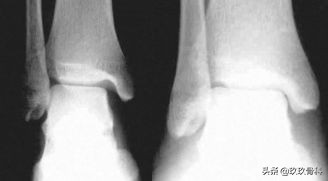

辅助检查

- X线 踝关节正侧位(必要时应加照踝穴位)

应力位片

鉴别诊断

- 内外踝骨折